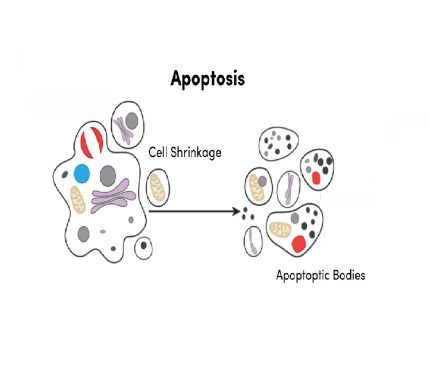

- آپوپتوز